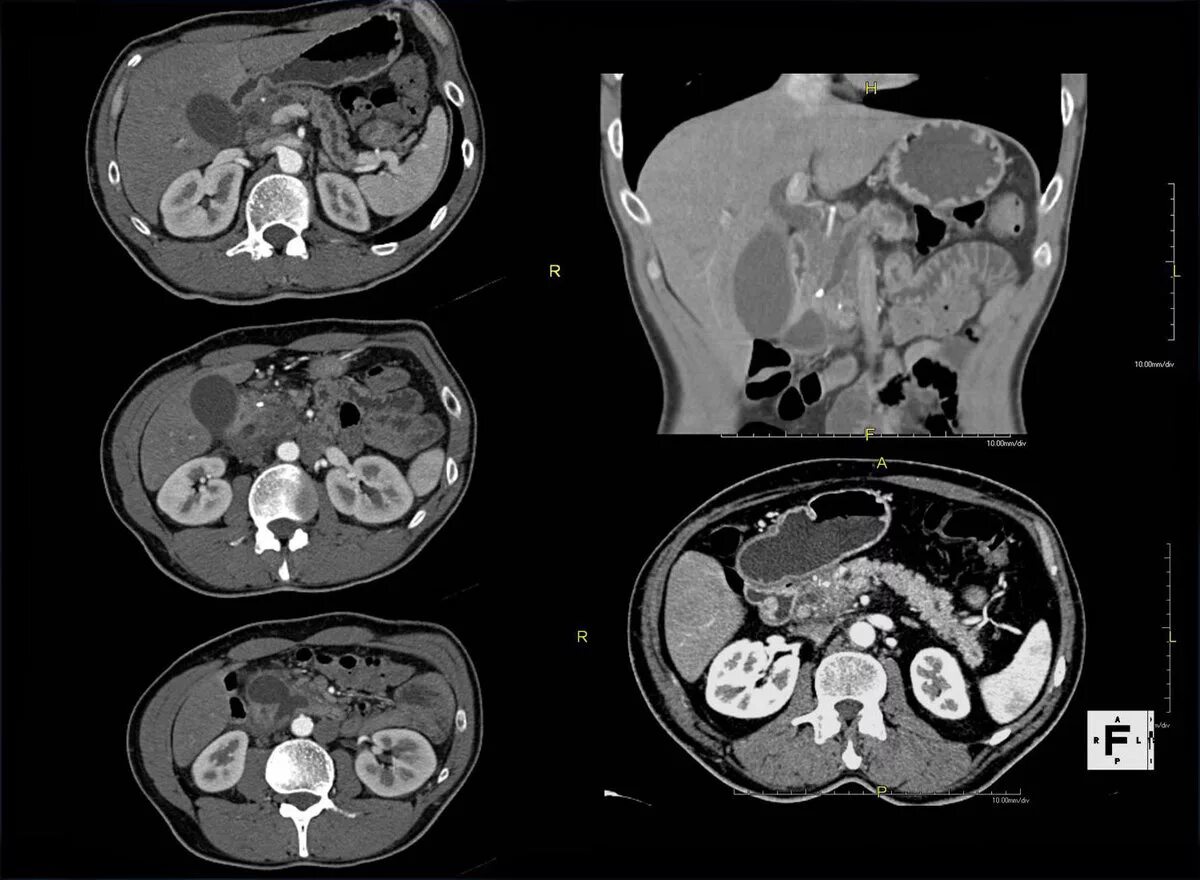

Подготовка к кт грудной и брюшной полости